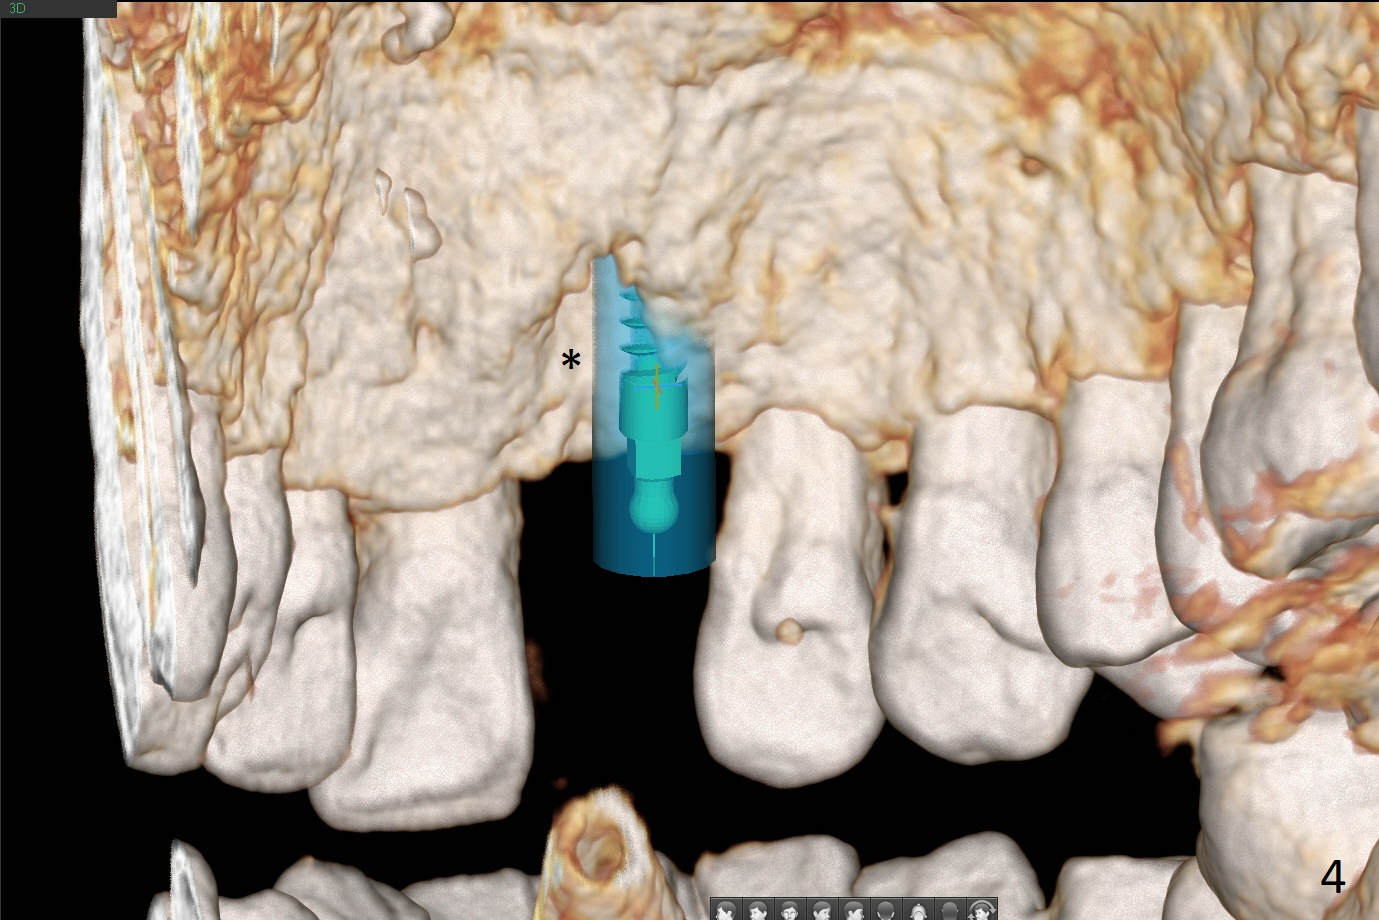

A 50-year-old man loves chewing bone and crab leg. The tooth #19 was extracted due to fracture 1.5 years ago (Fig.1). To reduce abutment screw loosening, IS guide will be used to create osteotomy, while a Tatum implant will be place initially with the guide (Fig.2). There appears no screw loosening associated with Tatum implants. The ridge at #8 is atrophic; a 2.5x10 mm Mini-implant will be placed palatal (Fig.3). The mesiopalatal defect (Fig.4 (lingual view) *) will be bone grafted after implant placement. Incision will be made after the 1st drill for access. The guide will be made with gingival clearance. A piece of 6-month membrane will be cut with a hole buccally to cover the bone graft and slide through the implant.